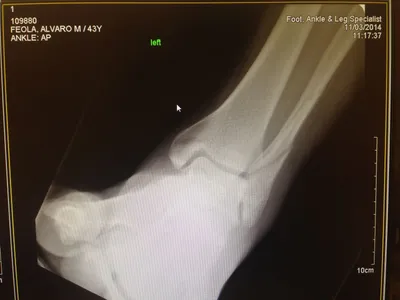

X-ray of Non Displaced Posterior Malleolar Fracture

Both the lateral and medial malleolus with fractures with the lateral malleolar fracture classified as a Weber B (at the level of the ankle joint) and the medial malleolar fracture almost transverse (Left x-ray). This is indicative of a Supination External Rotation (SER IV) injury. The fractures are repaired using open reduction with internal fixation (ORIF) technique and fixated with screws and a surgical fractue plate located at the fibular (Right x-ray).

A bimalleolar fracture is a fracture of the ankle that involves the lateral malleolus and the medial malleolus. Studies have shown that bimalleolar fractures are more common in women, people over 60 years of age, and patients with existing comorbidities. Surgical treatment will often be required, usually an Open Reduction Internal Fixation (ORIF). This involves the surgical reduction or realignment of the fracture followed by the implementation of hardware to aid in the healing of the fracture. Usually a plate and screws will be used on the fibular fracture and screws, screws and pins, pins or tension band will most commonly be used on the medial malleolus fracture. A bimalleolar "equivalent" fracture is a fracture of the fibula with rupture of the superficial and deep portion of the deltoid ligaments leaving the medial malleolus intact. Surgical management is common due to the instability of the fracture and displacement of the talus laterally.

The x-ray images below demonstrate another case of a bimalleolar ankle fracture in both and oblique view (left) and anterior - posterior view (right).